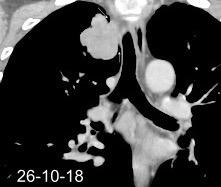

Marzo 2014: Perforación longitudinal distal secundaria a episodio de vómito (síndrome de Boerhaave). Derrame pleural izdo. que evoluciona a empiema.

Wang C-T et al. Tension hydropneumothorax in a Boerhaave syndrome patient: A case report . World J Emerg Med, 2021. Katabathina V et al. Nonvascular, nontraumatic mediastinal emergencies in adults:a comprehensive review of imaging findings. Radiographics. 2011.